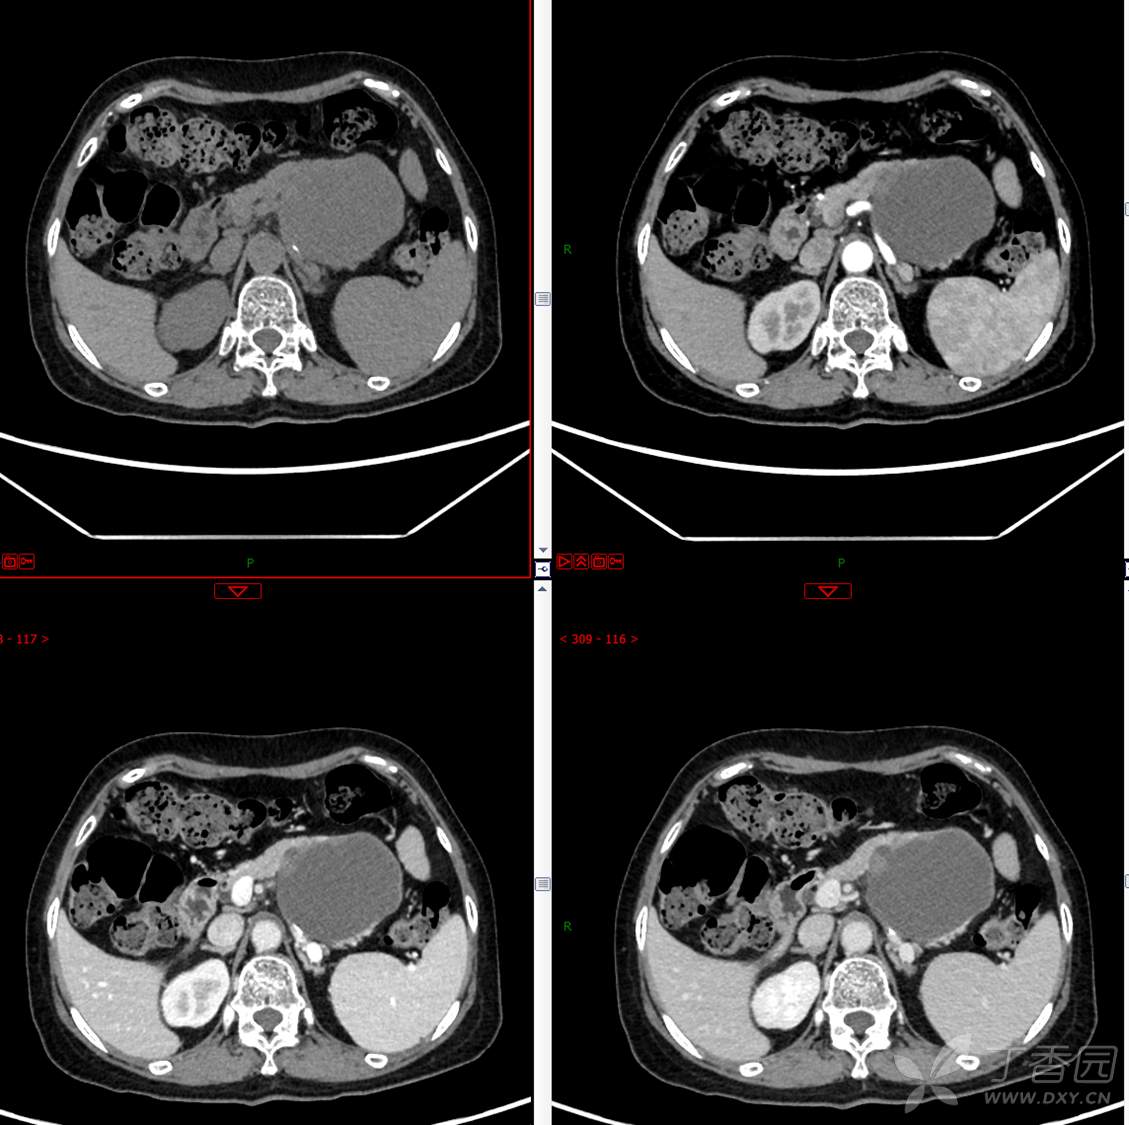

主 诉:发现胰腺占位性病变3月

现病史:患者3月前就诊于**市人民医院行腹部增强CT发现胰尾占位性病变,无腹痛、腹胀,无恶心呕吐,无黄疸,无呕血黑便,无胸闷憋气,无寒战高热,未行特殊治疗